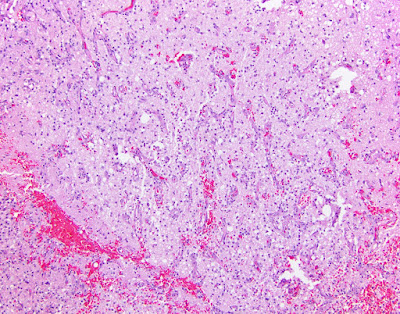

Astroblastoma

This is a rare, as yet ungraded, cerebral tumor of childhood. It is composed of cells that are GFAP positive and have broad, non-tapering processes radiating toward central blood vessels (astroblastic pseudorosettes). The border with adjacent brain is pushing, not infiltrative. Hyalinized vessels (as seen below) are a hallmark of astroblastoma. No ependymal features have been identified in studies of this unusual entity.